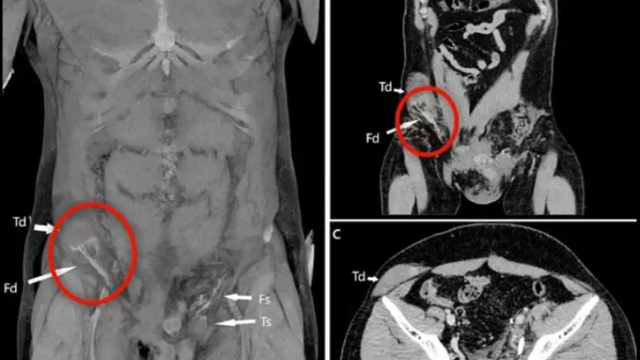

Um homem teve seu testículo deslocado para região do abdômen após sofrer um acidente. O caso aconteceu na Itália e foi publicado através da revista médica BMJ Case Reports em setembro deste ano. Segundo a revista, o italiano havia sofrido um acidente de moto.

Com o impacto, o testículo direito do homem saiu do local onde fica, no saco escrotal, por uma cavidade na região da virilha e subiu até o abdômen. A identidade do rapaz não foi revelada por conta da ética médica, apenas que ele tinha por volta dos seus 20 anos.